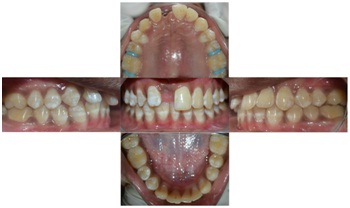

A 12-year-old boy accompanied by his parents reported to the Department of Pedodontics and Preventive Dentistry, with the chief complaint of tooth loss in the upper front region one and half years ago in a road accident. History revealed that the patient had a bicycle accident one and half years earlier and one of the anterior tooth was avulsed and patient brought an avulsed tooth along with him, to replace the saddle. Clinical examination revealed space loss in relation to the maxillary right central incisor, class I molar relation on both sides and maxillary arch oval in shape [Table/Fig-1]. Clinically a 4 mm space loss in relation to 11 was confirmed with intraoral periapical radiograph (IOPA) [Table/Fig-2]. The case was undertaken for space regaining with modified 2 by 3 fixed appliances, then followed by fixed functional space maintainer.